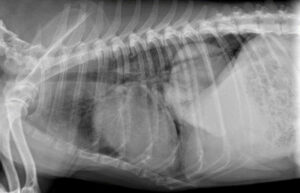

↑ 上の写真は、腎結石から尿管結石が連なっている症例のレントゲン写真です。・◆ 左の大きな白い部分が、腎結石です。・◆ 腎臓の右に続く線状の白い部分は、尿路結石です。  参照サイト:https://00m.in/dsGDy…